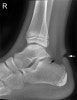

X-ray : 아킬레스건 파열(Achilles tendon tear)